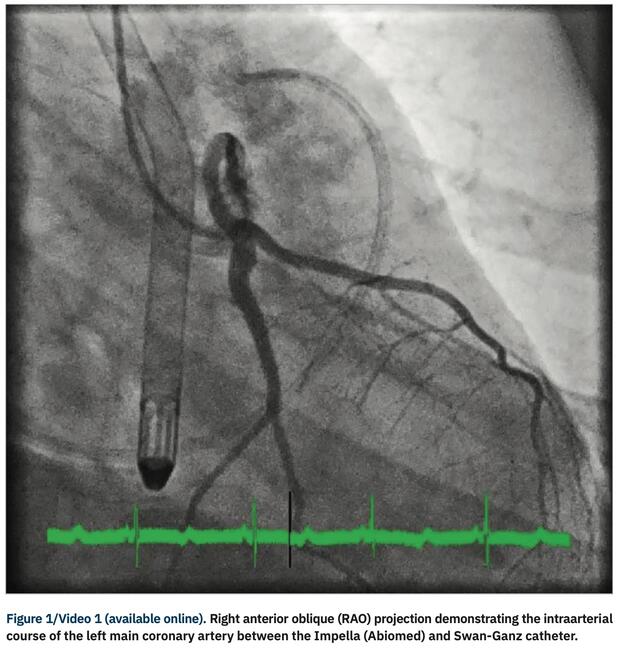

Malignant or interarterial course of the large epicardial coronary arteries can cause myocardial ischemia, angina, acute coronary syndromes, congestive heart failure, or sudden cardiac death. Interarterial course occurs when the coronary artery originates from the inappropriate sinus. We describe a case of an 18-year-old healthy collegiate basketball player who presented with ventricular fibrillation and cardiogenic shock due to an interarterial and intramural course of an anomalous left coronary artery without an ectopic origin.